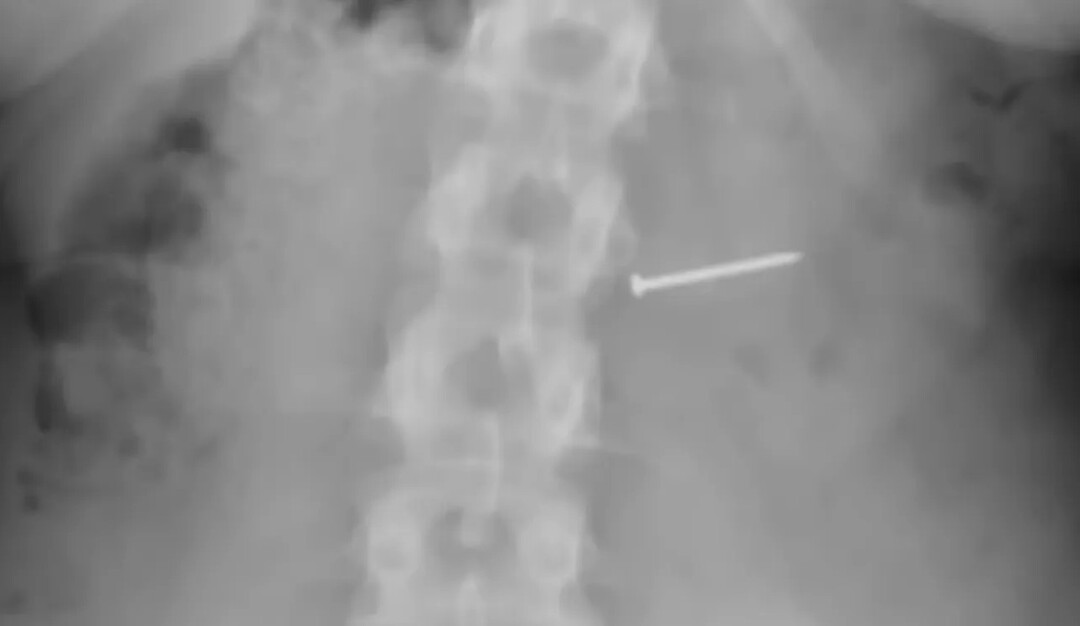

| 버클리가 삼킨 못./유튜브 |

버클리는 자신도 모르게 한 입 베어 물었고 그 중 못 한 개를 삼켜버리고 공표에 질렸다.